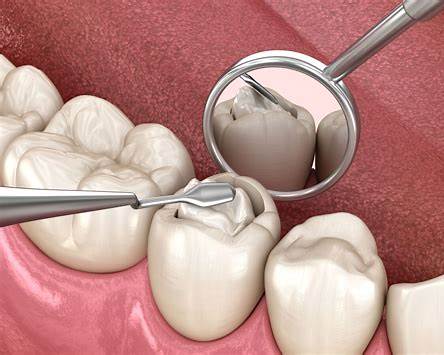

The decayed portion of the tooth is carefully removed to create a clean, healthy surface for the filling.

After placement, the filling is shaped and polished to ensure a natural bite and comfortable fit.

A dental filling is a routine and minimally invasive procedure designed to restore and protect your tooth.

A dental filling is a restorative treatment used to repair a tooth damaged by decay or minor fractures.